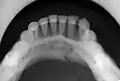

occlusal radiograph of a mandibular parasymphysis fracture

Parasymphyseal fractures are defined as mandibular fractures that involve a region bounded bilaterally by vertical lines just distal to the canine tooth.[18]